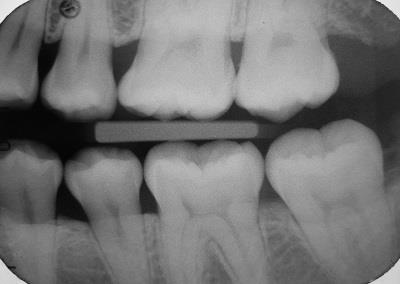

Dental Radiographs - Part 1: Bite-Wings and Periapicals

Implant dentistry has become the standard of care in the 21st Century.  So, when should you remove a tooth and replace it with an implant? This is certainly one of the biggest dilemmas a patient and their dentist can face. As a periodontist who is trained to save teeth, I still believe there is...  Read More